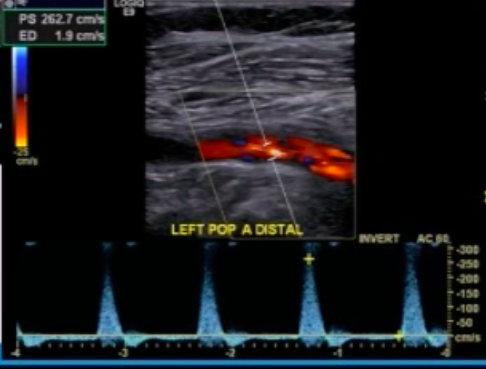

Diabetic with LE ulcers has arterial DUS images shown below.

How will you report the findings in the images?

75-99% occlusion in PTA

PSV near lesion in PTA is ~160 cm/s, which is _>_4x proximal flow (~40 cm/s, in distal popliteal artery)